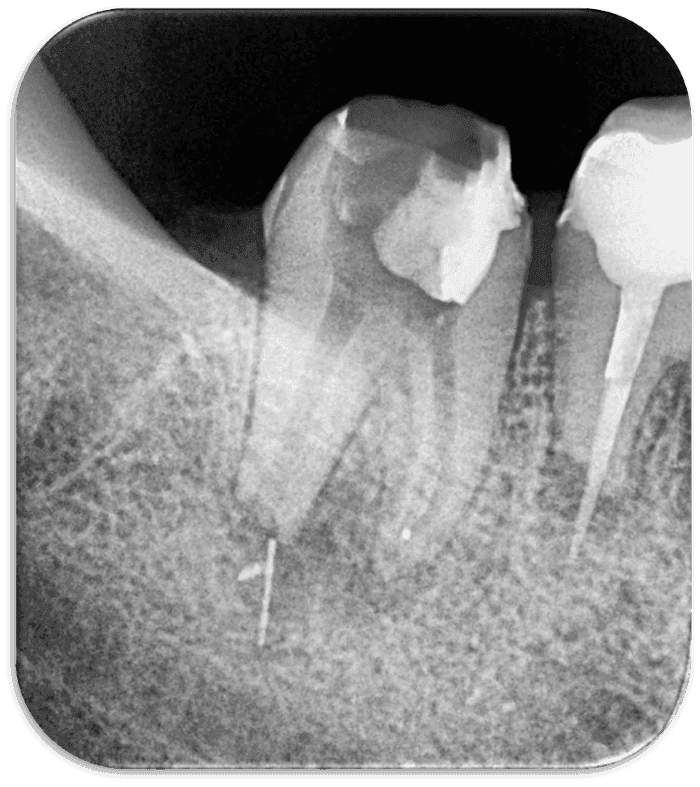

Kuvvet uyguladığımızda eğenin bir kısmı kırılarak tel ilmik ile çıktı (RESİM 8). Kalan parça için RVG alındı ve parçanın lezyon içinde hareket ettiği ve distal kök ucundan uzaklaştığı anlaşıldı. Seans bitiminde kalsin yerleştirildi ve 3. randevu oluşturuldu.

RESİM 8: Kırılarak çıkan eğe parçası